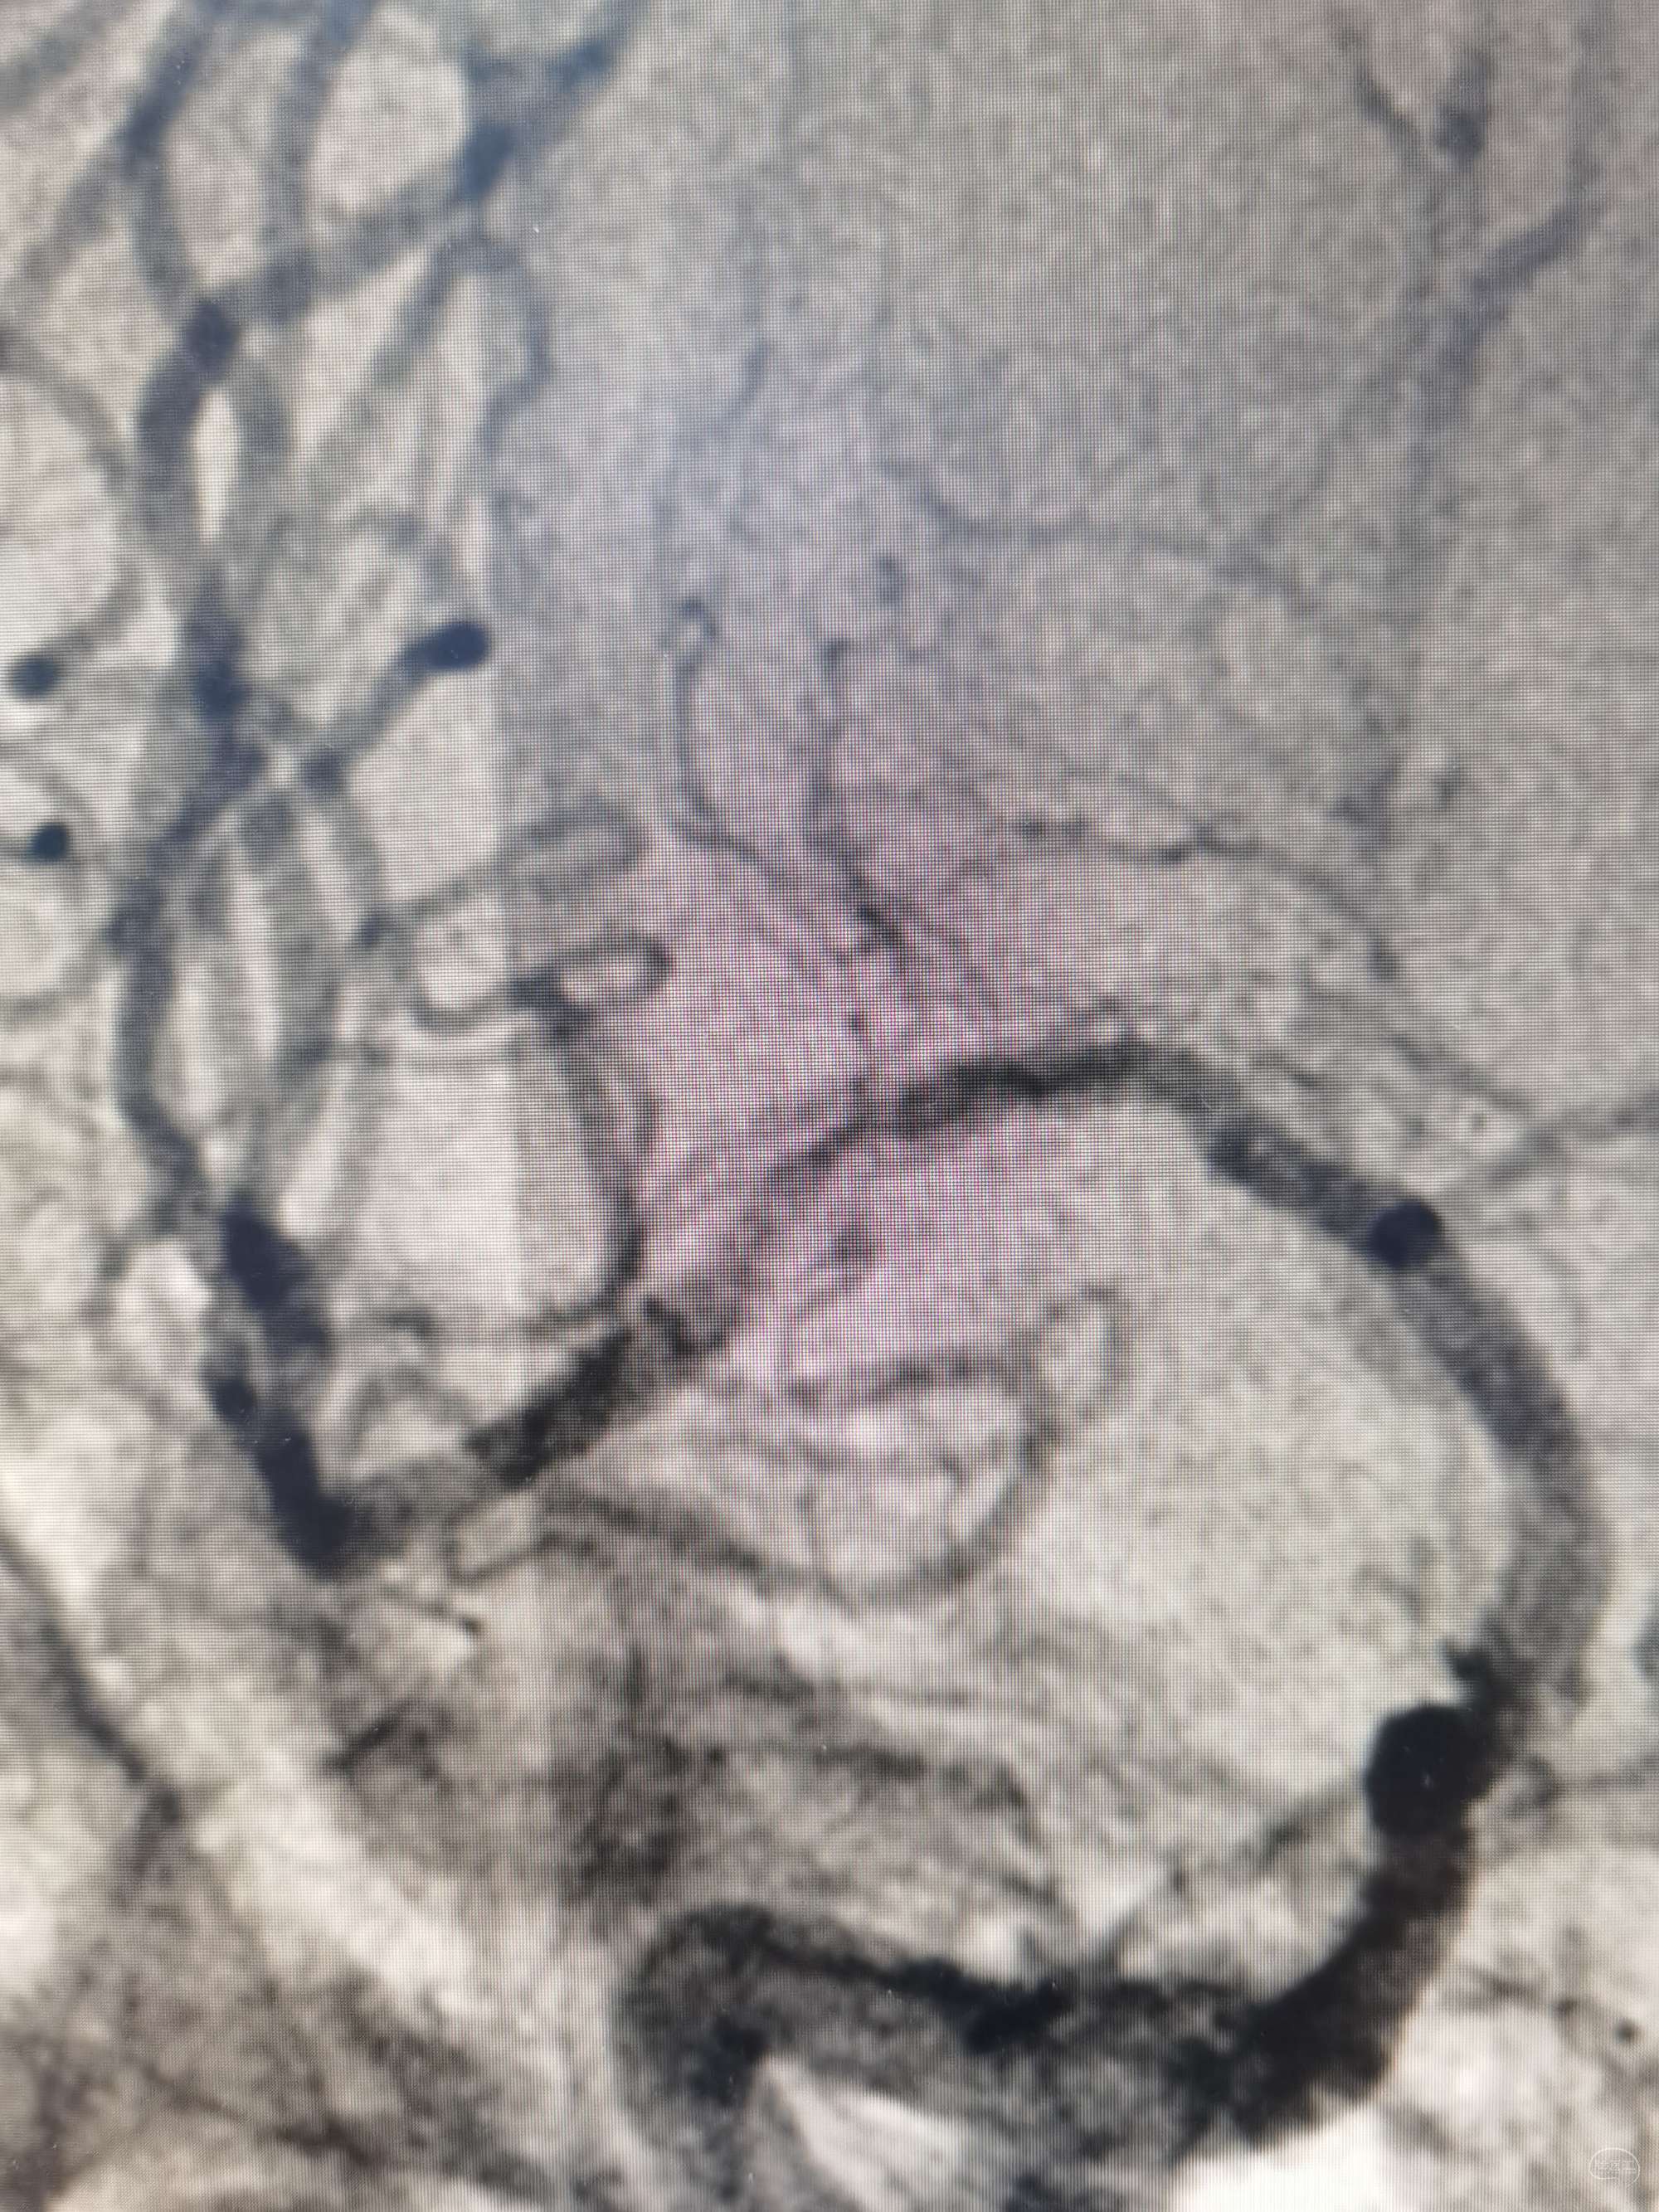

支架也放了还是取一把,取出小栓子1枚,再次造影:m1远端重度狭窄,微导丝再次通过后即可见远端血流差

1.5*15颅内球囊命名压缓慢扩张,缓慢泄

扩张后观察5min血流及局部情况

不行,替罗非班5ml经中间导管缓推后,持续静脉泵入

替罗非班后再看: